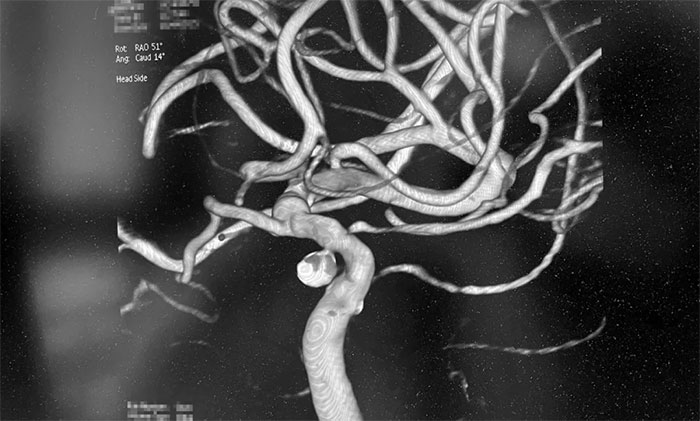

为进一步明确诊断,王大妈接受了全脑血管造影DSA检查,发现左颈内动脉眼动脉段动脉瘤(约3mm)伴左颈内动脉眼动脉段重度狭窄。神经内科4A病区主任席刚明教授、神经内科4A病区副主任王贵平博士会诊指出,左颈内动脉眼动脉段重度狭窄就是王大妈右侧肢体活动不利等症状的“元凶”,如不及时解除血管狭窄,一旦颈内动脉闭塞,就会发生脑梗死!此外,一旦脑动脉瘤破裂,将导致蛛网膜下腔出血!“左颈内动脉眼动脉段重度狭窄”和“左颈内动脉眼动脉段动脉瘤”就像潜伏在患者体内的“不定时炸弹”,随时都有被“引爆”的风险,导致严重致残甚至危及生命。

▲ 脑动脉狭窄合并脑动脉瘤

术中,席刚明教授在王贵平博士及医护团队密切配合下,先对左颈内动脉C6段动脉瘤进行弹簧圈栓塞治疗,经Echelon-10微导管送入弹簧圈,成篮满意后暂不解脱;随后,微导丝引导球囊扩张导管头端置于左侧大脑中动脉M1段,球囊部分覆盖左颈内动脉C6狭窄段,进行球囊扩张,扩张后见左颈内动脉C6段狭窄明显改善,随后释放支架于左颈内动脉C7段至C4段,造影见左颈内动脉、左大脑中动脉、左大脑前动脉显影可。最后,继续栓塞动脉瘤,经Echelon-10微导管送入多枚弹簧圈,填塞满意后解脱,造影见动脉瘤基本不显影;复查造影,行3D造影见左颈内动脉、左大脑中动脉、左大脑前动脉显影可;行支架CT见支架成形满意,行XperCT未见颅内出血,手术圆满完成。